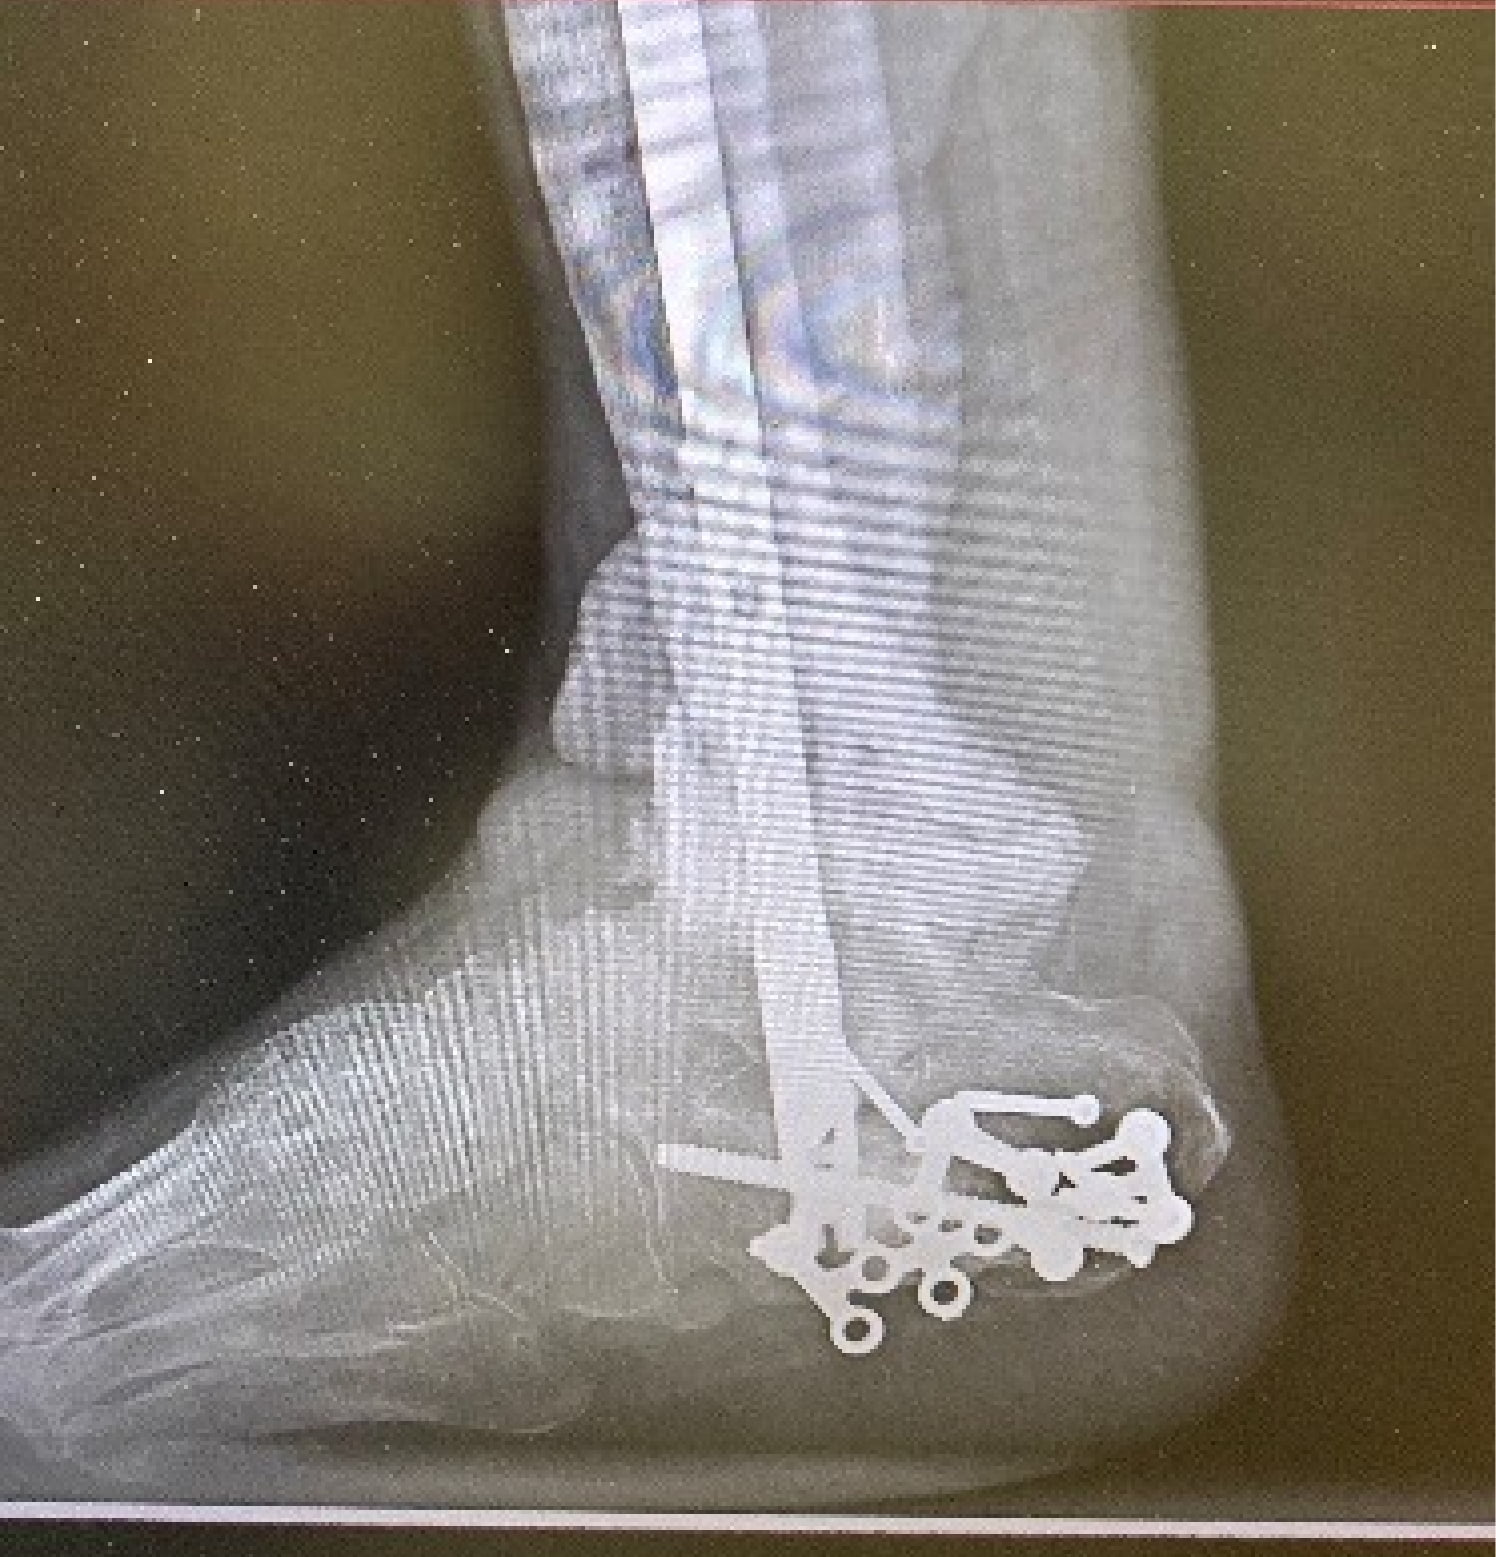

Then I had another complication when my bone was not fusing on its own. A piece of my fibula came out of place and started protruding from the skin, requiring yet another surgery. I was so heartbroken at this outcome that I was determined to move forward with the amputation. One last option was proposed to save my foot: it was recommended to insert a rod that would span from the heel to the mid tibia in order to reinforce the remaining bone. This procedure was especially complicated because I had shattered my calcaneus bone several years prior and now had metal holding it together. They were able to get around the metal in the calcaneus to insert the rod. I underwent a few more weeks of antibiotics to ensure there was no recurrent infection.